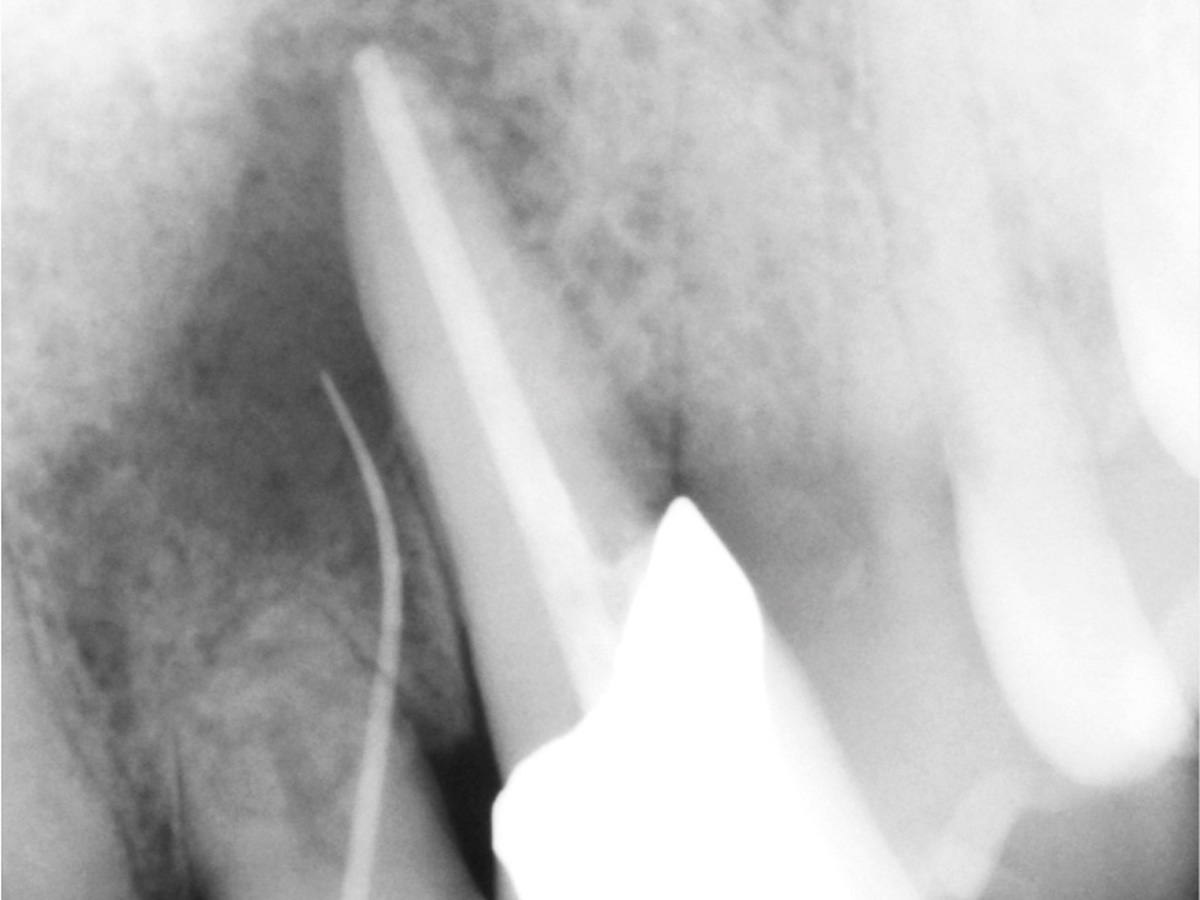

Abbildung 2

Radiologische Ausgangssituation 22, 23.